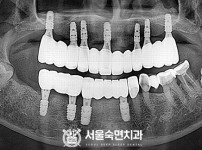

상악동거상술, 뼈이식 / 숙면임플란트 13개 - 오스템임플란트 (이*웅님)

해당 게시물은 의료법 제56조에 의거하여 로그인 후 열람이 가능합니다.

구분 임플란트